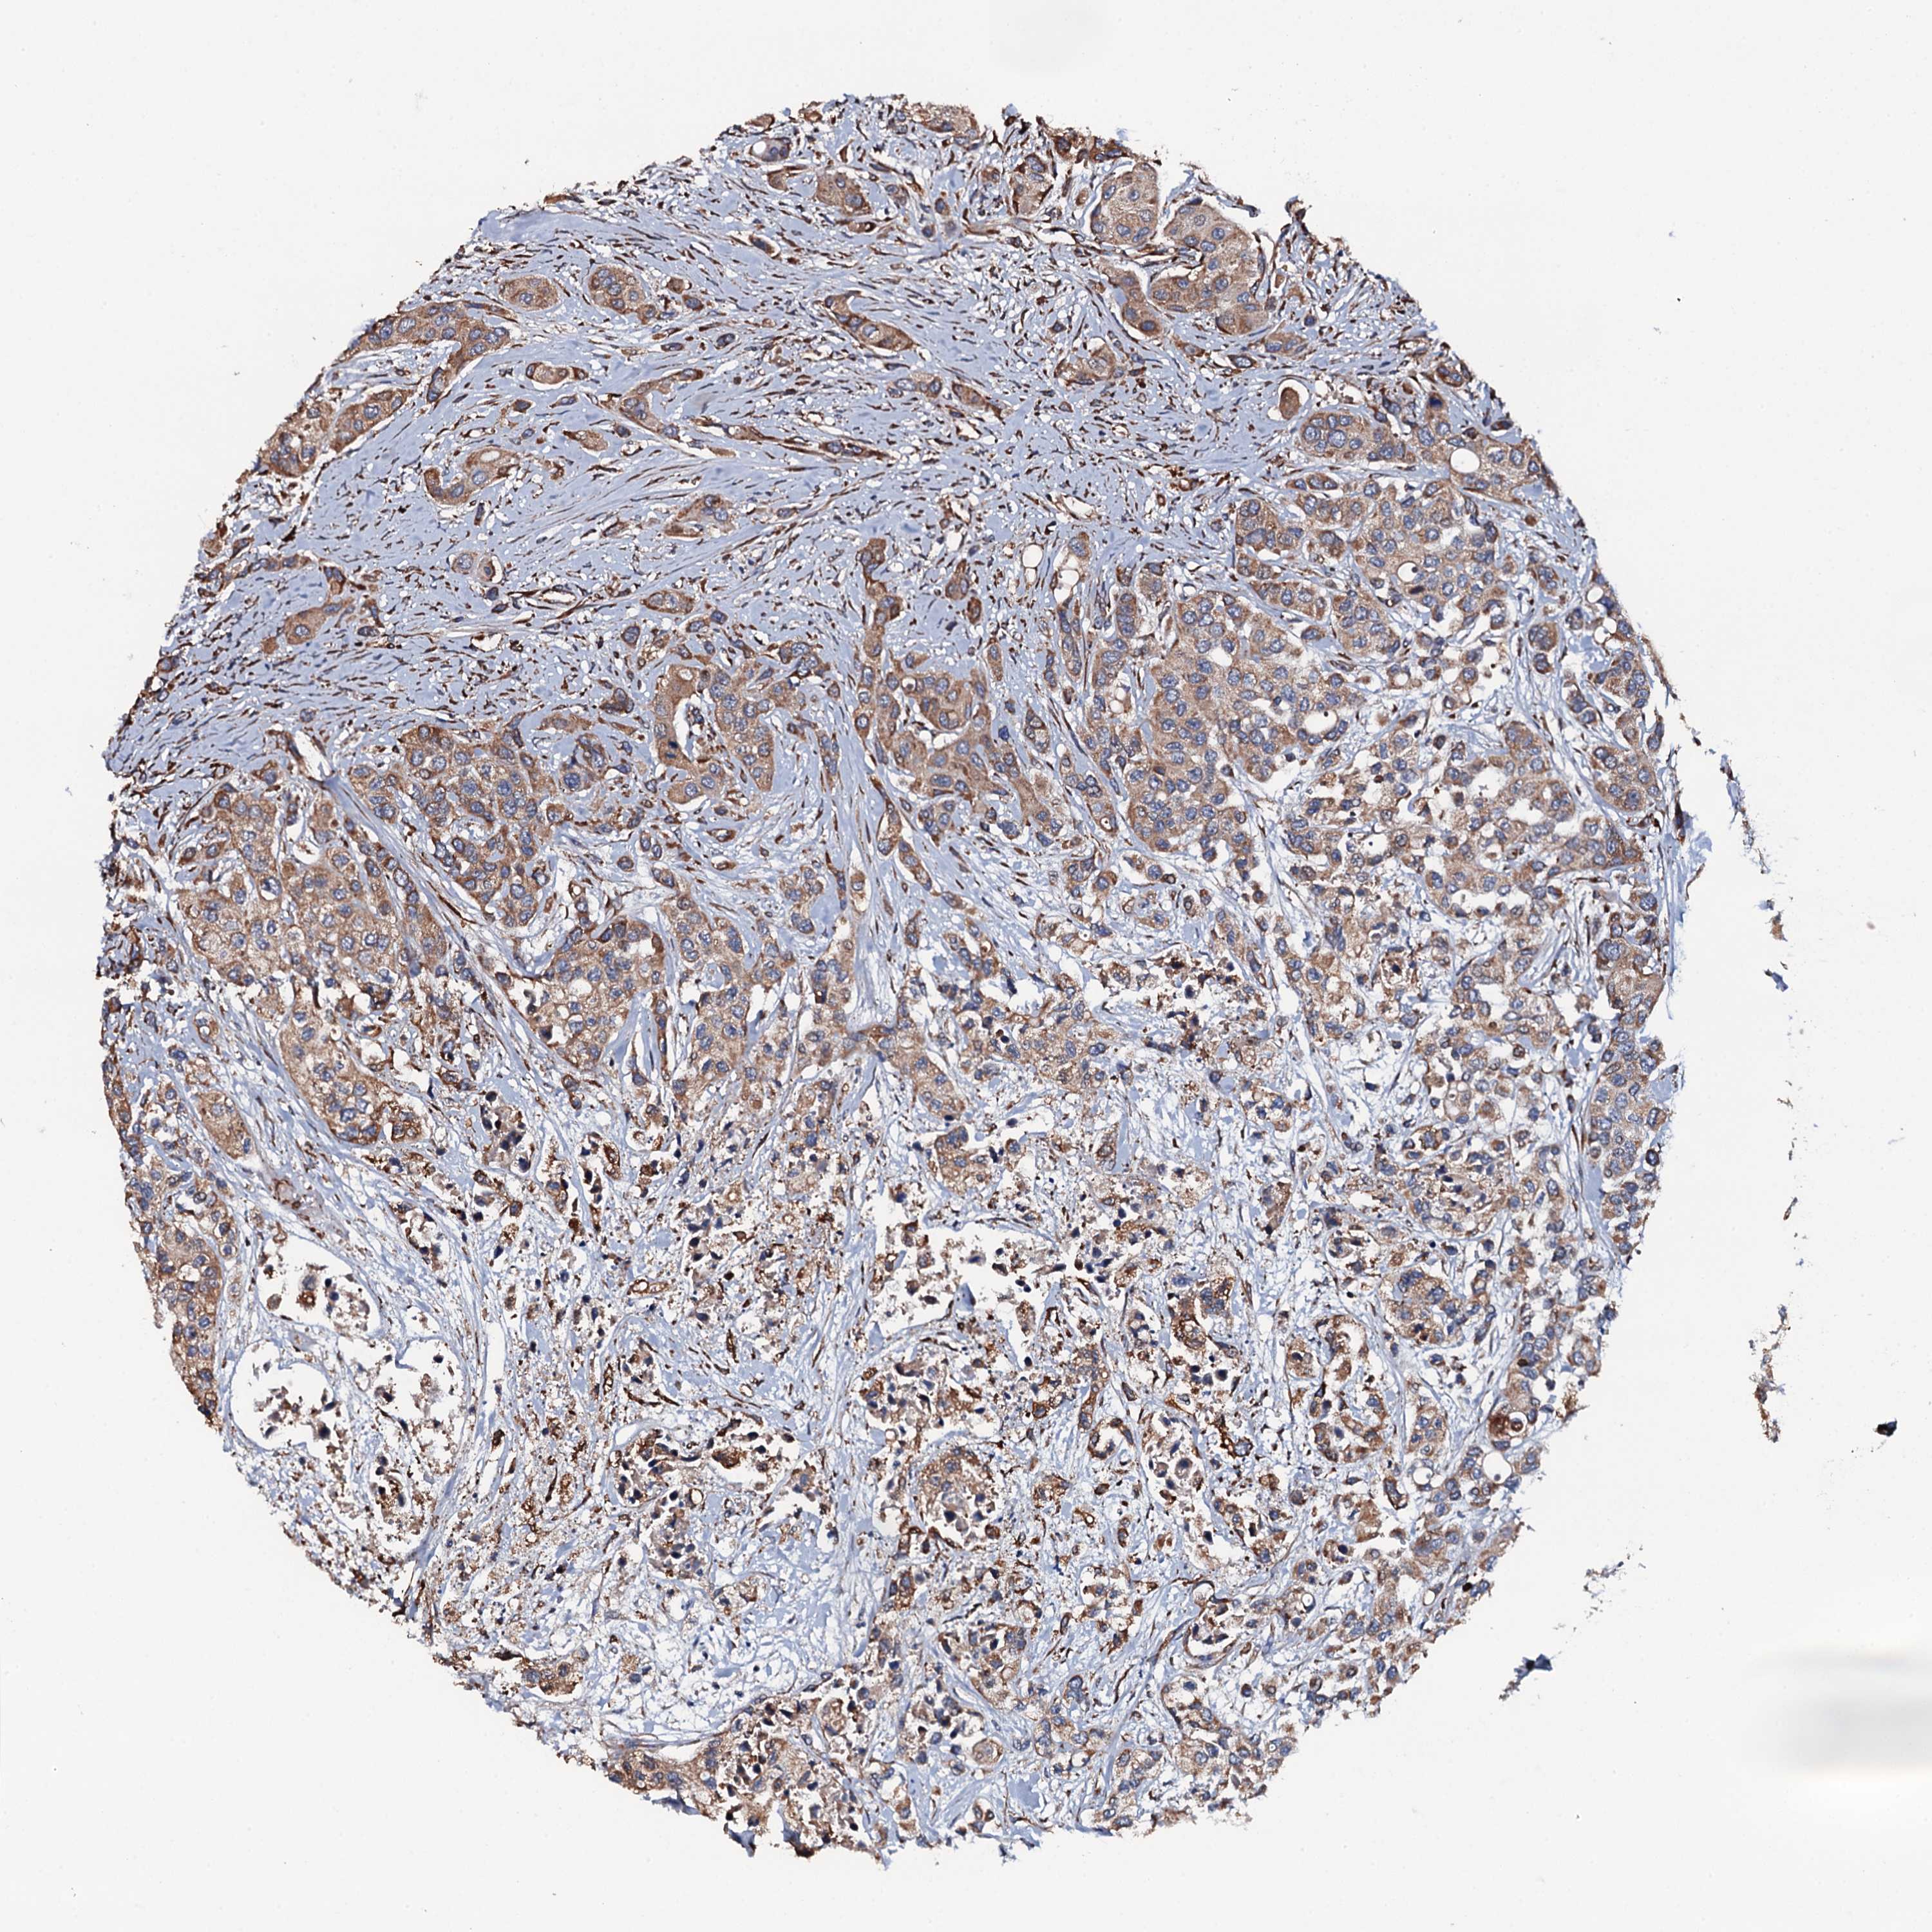

UROTHELIAL CANCER - Protein expressioni

A mouse-over function shows sample information and annotation data. Click on an image to view it in a full screen mode. Samples can be filtered based on level of antibody staining by selecting one or several of the following categories: high, medium, low and not detected. The assay and annotation is described here.

Note that samples used for immunohistochemistry by the Human Protein Atlas do not correspond to samples in the TCGA dataset.

Antibody stainingi

Antibody staining in the annotated cell types in the current human tissue is reported as not detected, low, medium, or high, based on conventional immunohistochemistry profiling in selected tissues. This score is based on the combination of the staining intensity and fraction of stained cells.

Each image is clickable and will lead to virtual microscopy that enables deeper exploration of all samples and also displays staining intensity scores, fraction scores and subcellular localization as well as patient and tissue information for each sample.

Antibody HPA040727

Staining

High

Medium

Low

Not detected

Intensity

Strong

Moderate

Weak

Negative

Quantity

>75%

75%-25%

<25%

None

Location

Nuclear

Cytoplasmic/membranous

Cytoplasmic/membranous,nuclear

Urothelial carcinoma, High grade

Urothelial carcinoma, Low grade